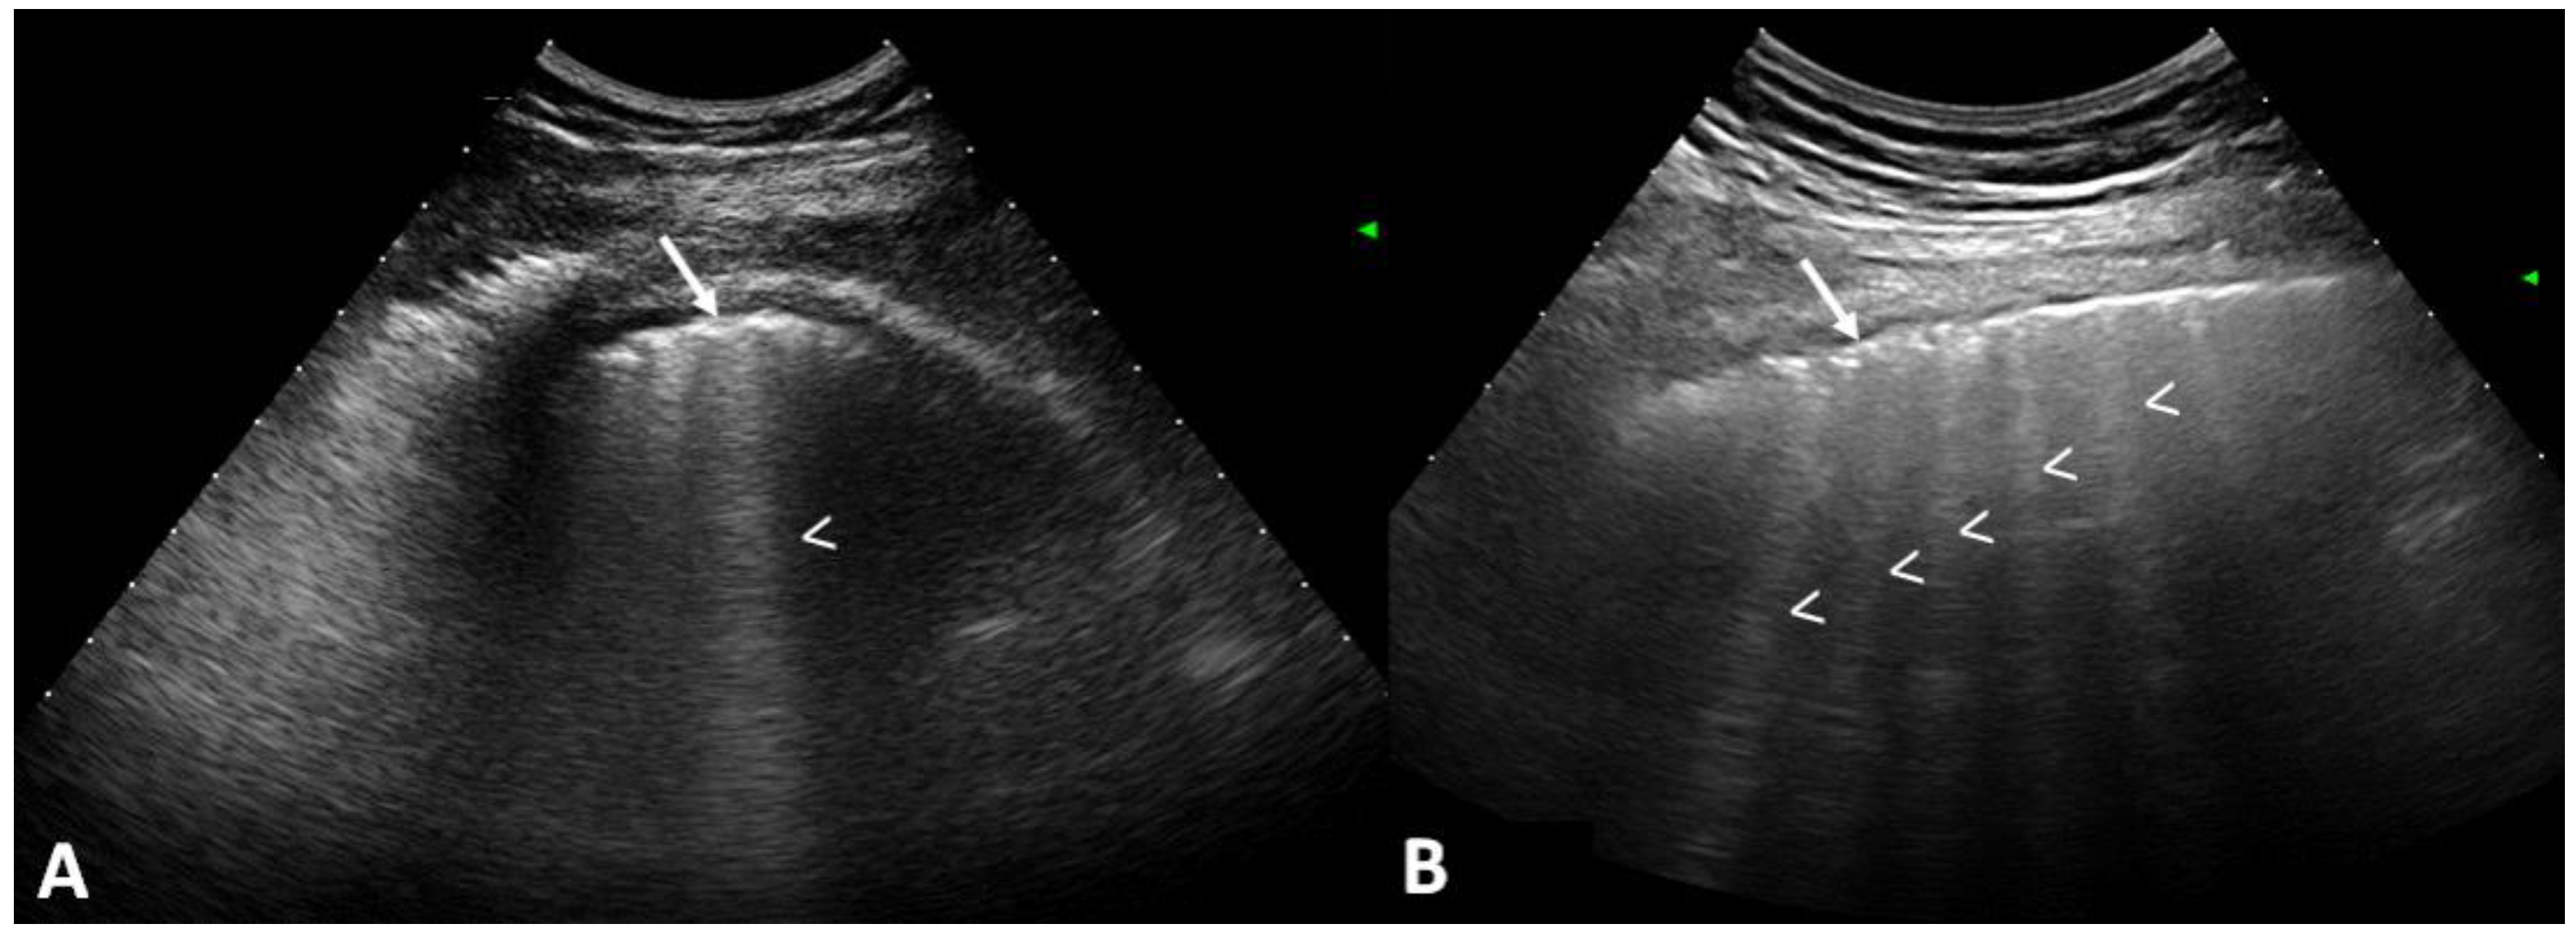

- Pinal-Fernandez, I.; Pallisa-Nuñez, E.; Selva-O’Callaghan, A.; Castella-Fierro, E.; SimeOn-Aznar, C.P.; Fonollosa-Pla, V.; Vilardell-Tarres, M. Pleural irregularity, a new ultrasound sign for the study of interstitial lung disease in systemic sclerosis and antisynthetase syndrome. Clin. Exp. Rheumatol. 2015, 33, S136–S141. [Google Scholar]